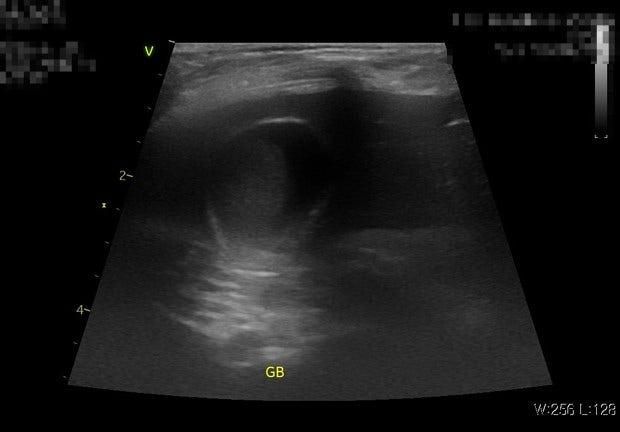

담낭의 슬러지가 있으면서 부분적으로 담낭에 있는 담즙이 끈적거리는 경우는 우루사와 같은 약을 쓸 수 있지만.

탐나의 완전 폐색이나 담낭 점액종 같이 담낭이 단단하게 굳어버린 경우는 우루사 같은 약을 쓰면 더 심해질 수도 있습니다.

지금 초음파 그림 보면 담낭이 그렇게 커 보이지도 않고 담낭자백종과 같은 양상이 확인이 되지 않으니 우루사를 써 볼 수 있지만